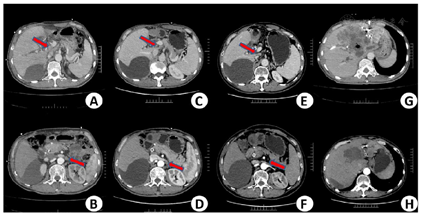

考虑到患者较年轻且患者及家属治疗欲望强烈,希望予以手术根治。为防止患者术后残肝脏体积不足发生肝衰竭,目前国内外多数学者主张采用术前行保留侧肝脏的PTCD和(或)切除侧肝门静脉栓塞(portal vein embolization,PVE)以使保留侧肝脏获得代偿性增生从而降低广泛肝切除的危险性[3]。4月3日患者于我科行PVE,术中予以生物胶+碘油+弹簧圈组合充分封堵门静脉左支主干。4月16日复查CT示左肝大片状碘油沉积,右肝代偿性增生(图3)。4月30日拟行胆管癌根治术,术中示肿瘤位于肝门汇合部,包裹肝十二指肠,大小约8 cm×4 cm,质硬,肝门部可见肿大淋巴结,无法行肝门部胆管癌根治术,遂行"剖腹探查术+开腹肝活检术+胆囊切除术"。术后免疫组化结果(图4)示肝脏: CA199 (小胆管+),CK19(小胆管+) ;CK7(胆管上皮+),HepPar-1(+),GPC3(-),AFP(-);CK20(-),K1-67(+,2%);淋巴结Kappa(+),Lambda(+),CK(-)。

根据"2020 NCCN肝胆癌指南",对于不可切除的胆管细胞癌,首选为全身治疗。对于黄疸患者,在切除和全身治疗前考虑进行胆管引流,胆道减压后考虑行CA19-9基线检查。根据美国癌症联合委员会(American Joint Committee on Cancer,AJCC)第8版肝内胆管细胞癌分期系统,本病例诊断为肝门部胆管细胞癌,T4N1M0 IIIC期,外科评估无法切除(2020年4月30日)。患者因手术未能切除导致疾病进展,7月因胆管梗阻再次入院,检测CA19-9为185.99 IU/ml,TBIL为169.4 umol/L,DBIL为126.8 umol/L。为解决梗阻性黄疸症状,于7月6日行PTCD引流并置入3根引流管。随着部分胆管再通,患者一般情况好转,拟对肝内病灶进行治疗。于10月11日行肝动脉化疗栓塞术(transcatheter arterial chemoembolization,TACE),造影示肝右叶见一团块状浅淡肿瘤染色,主要由肝右动脉供血,术中用药为吉西他滨1.2 g,洛铂50 mg,48%碘化油5 ml。术后予以保肝、退黄等对症处理。 11月复查CT示肿瘤稍有变大,且肝门部及腹膜后可见肿大淋巴结。结合患者病情,建议患者行卡瑞利珠单抗(200 mg静脉滴注,每3周一次)免疫治疗联合阿帕替尼(250 mg口服,1次/d)靶向治疗,患者同意。2020年11月至2021年9月,患者入院接受卡瑞利珠单抗治疗14次,治疗后病灶明显缩小,且液化坏死明显,根据实体瘤改良疗效评估标准(mRECIST)评估为完全缓解(complete remission,CR);其中在2021年5月及2021年9月CT随访中显示肿大淋巴结已明显减小或消失(图5)。CA19-9是胆源性肿瘤关系密切的标志物,CA19-9值的降低能够预测肿瘤大小的减少,可用于潜在地判断对当前治疗的反应[1,2]。此时,CA19-9指标也明显降低并维持正常水平(图6)。